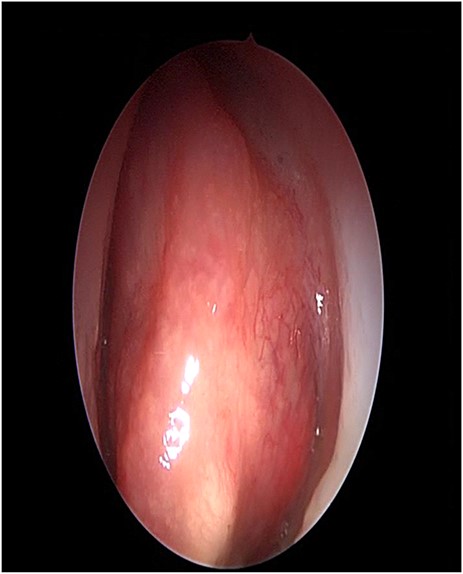

A 34-years-old man presented with left-sided facial pain, headache and nasal obstruction for a long duration, with no history of bleeding per nose, nor blurring of vision. Upon examination, there was a large left nasal cavity bony outgrowth pushing the middle turbinate and pushing the nasal septum to the right side (Fig. 1). CT scan of the paranasal sinuses showed a large mass centered in the left anterior ethmoid sinus, the mass measures 3.7 × 2.9 cm (trans-axial) (Fig. 2) and 3.7 × 5.2 cm (coronal) (Fig. 3), it has a heterogeneous density with calcified and soft-tissue component. The calcified component is in the periphery with central soft tissue density. The mass resulted in remodeling of adjacent bones with nasal septal deviation to the right, it extended superiorly to involve the frontal sinuses as well as invading the left cribriform plate and intracranial extension (Fig. 4), it extended inferiorly displacing the medial wall of the left maxillary antrum. The medial aspect of the mass caused remodeling of the medial wall of the left orbital cavity with bulging and displacement of the medial rectus muscle. The mass resulted in obstruction of the left frontal sinus.

Nasal endoscopy image showing a bony mass attached to the left middle turbinate pushing the septum to the right.